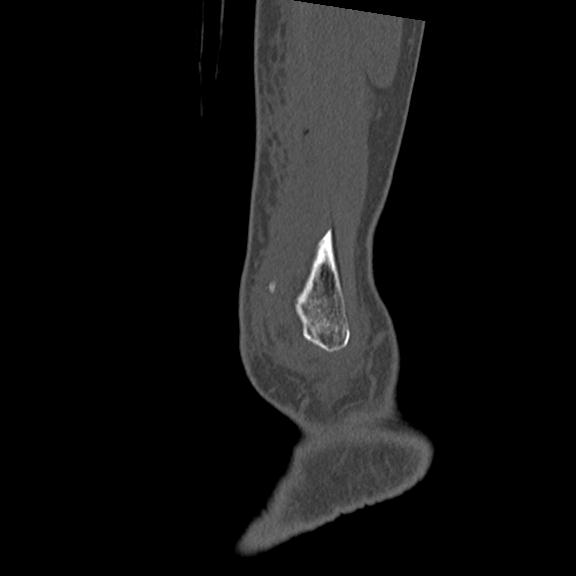

56476 8/28 4R 1/21 2R 左足関節 デジカメ写真 72歳女性 右足関節AS